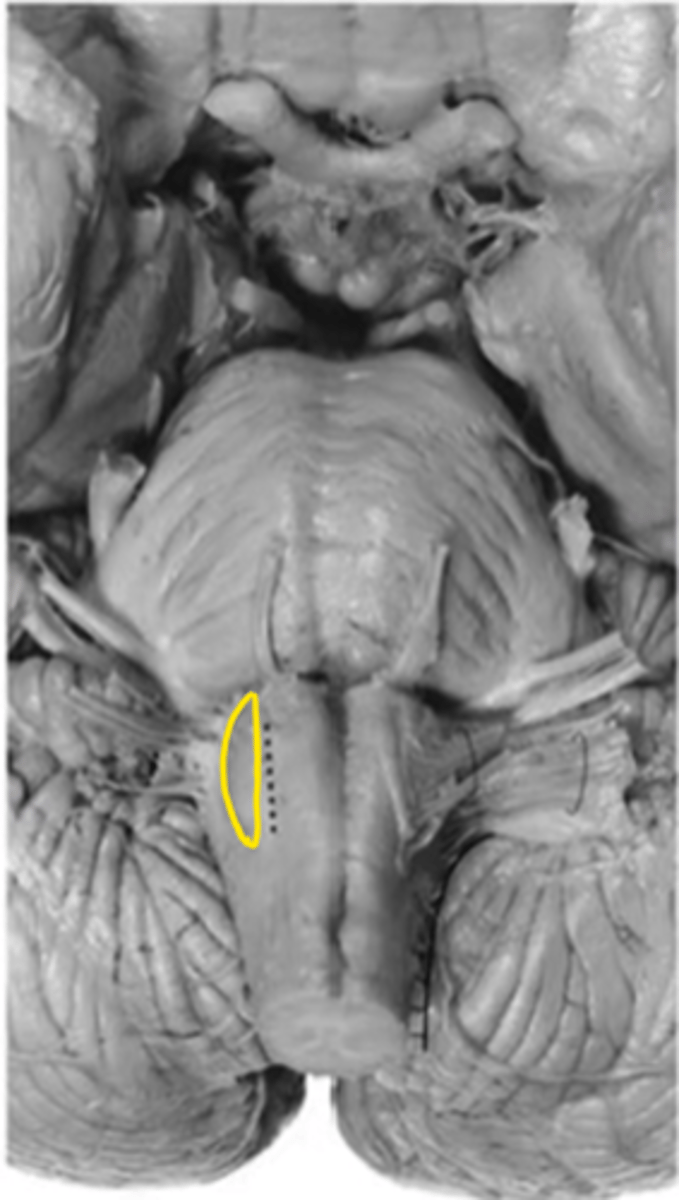

medullary pyramids

ID the structure

anterior median sulcus